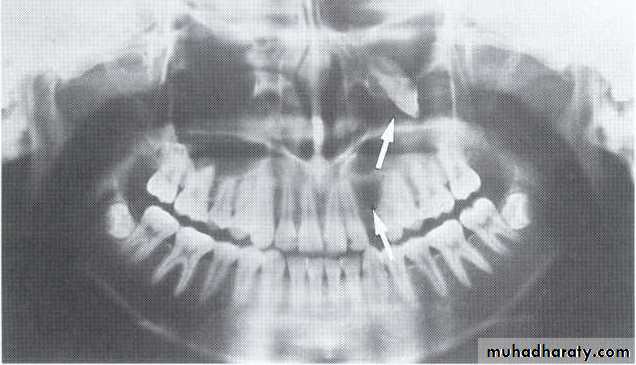

5-year-old boy showing the typical bilateral multilocular lesions of

cherubism affecting the mandible (arrowed).Multiple but separate radiolucent lesions

• Cherubism

*Hereditary & involve many members of the family.*Age; <20 years.

*Affect the jaw bone only.

*Bilateral, expansile, multiple, soap bubble-like radiolucencies in the mandible.

*Migration of teeth & tooth germ, without exfoliation or become loosed.